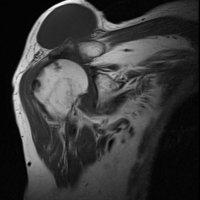

On physical examination, an AC joint cyst is a palpable fluid-filled mass. MRI scanning or a shoulder arthrogram should be obtained to evaluate the shoulder. Unenhanced MRI scans showing a large rotator cuff tear, a degenerated AC joint, and a large subcutaneous cyst adjacent to the AC joint is virtually patognomonic for the disease. Contrast administration on MR arthrogram will show the synovial fluid or intra-articular contrast extravasates from the glenohumeral joint into the subacromial bursa, into the AC joint, and then into an overlying cystic mass when a full-thickness rotator cuff tear is present, resembling a geyser spouting upwards.